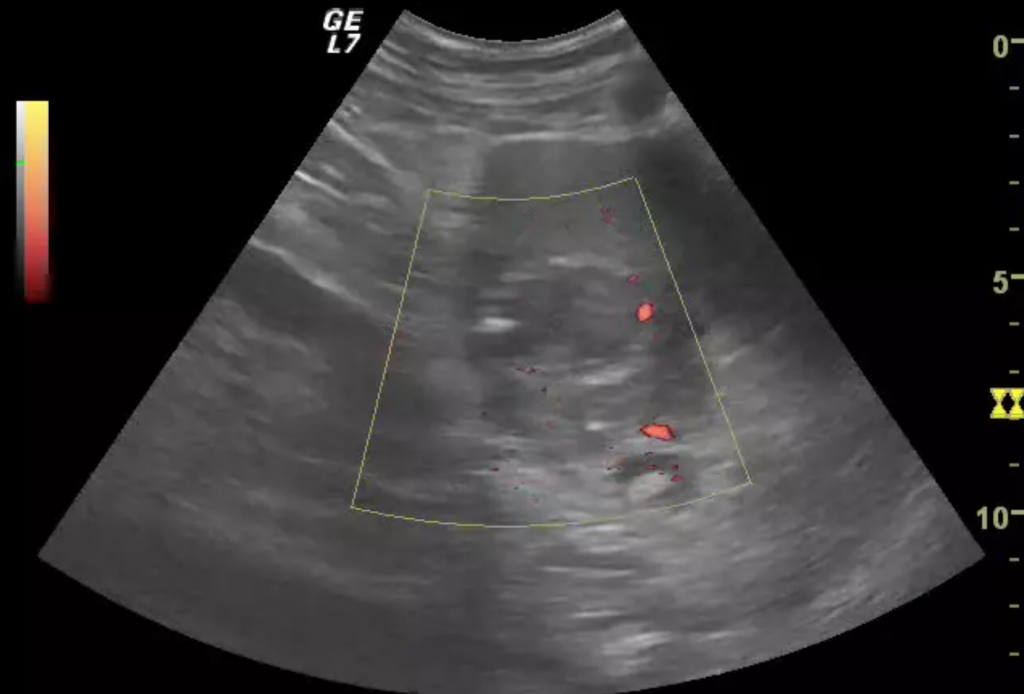

ЦДК сосудов почек: что это и как проводится

Раздел: Фотоэссе